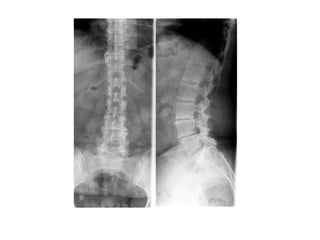

INCIDÊNCIA COLUNA LOMBAR

INCIDÊNCIAS ESCOLIOSE

COLUNA TOTAL ESCOLIOSE